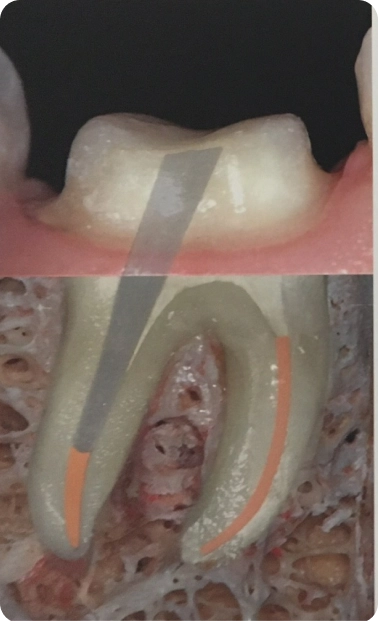

O tratamento de canal remove tecidos infectados ou danificados do interior do dente, aliviando a dor e prevenindo o aumento de infecções. Com nossa abordagem cuidadosa, restauramos sua saúde bucal e a funcionalidade do seu dente com o mínimo desconforto possível.

Desmistificamos o tratamento de canal, explicando como os avanços tecnológicos tornaram o procedimento muito mais confortável, eficaz e humanizado do que no passado.

A Endocardite Bacteriana é uma infecção bucal, por isso, a causa mais comum é a falta de higiene adequada na cavidade oral. Quando a cárie penetra no canal, as bactérias podem cair na corrente sanguínea e serem levadas até o coração. Por isso o tratamento de canal deve ser corretamente executado e acompanhado para não gerar uma infecção generalizada.